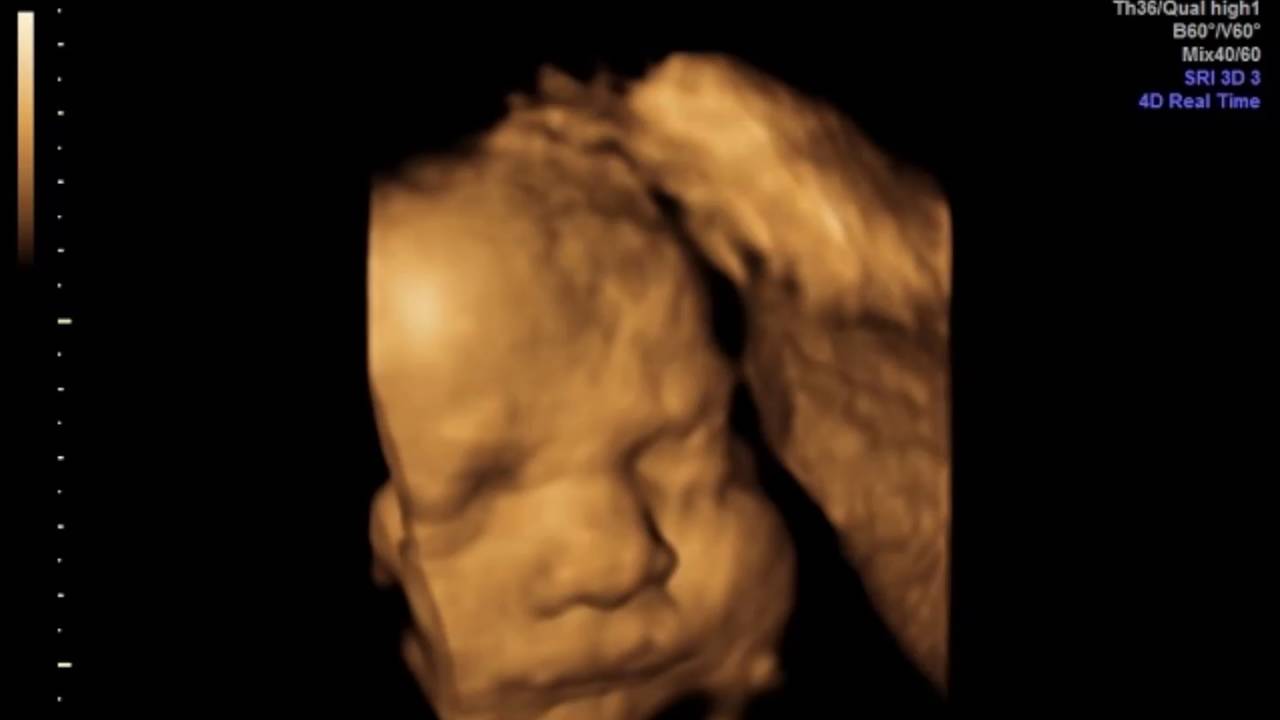

4 Boyutlu Ultrason

Gevher Nesibe Mahallesi Gök Geçidi No: 15 Kocasinan, 38070 Melikgazi, Kayseri

System Hospital Tüp bebek merkezi